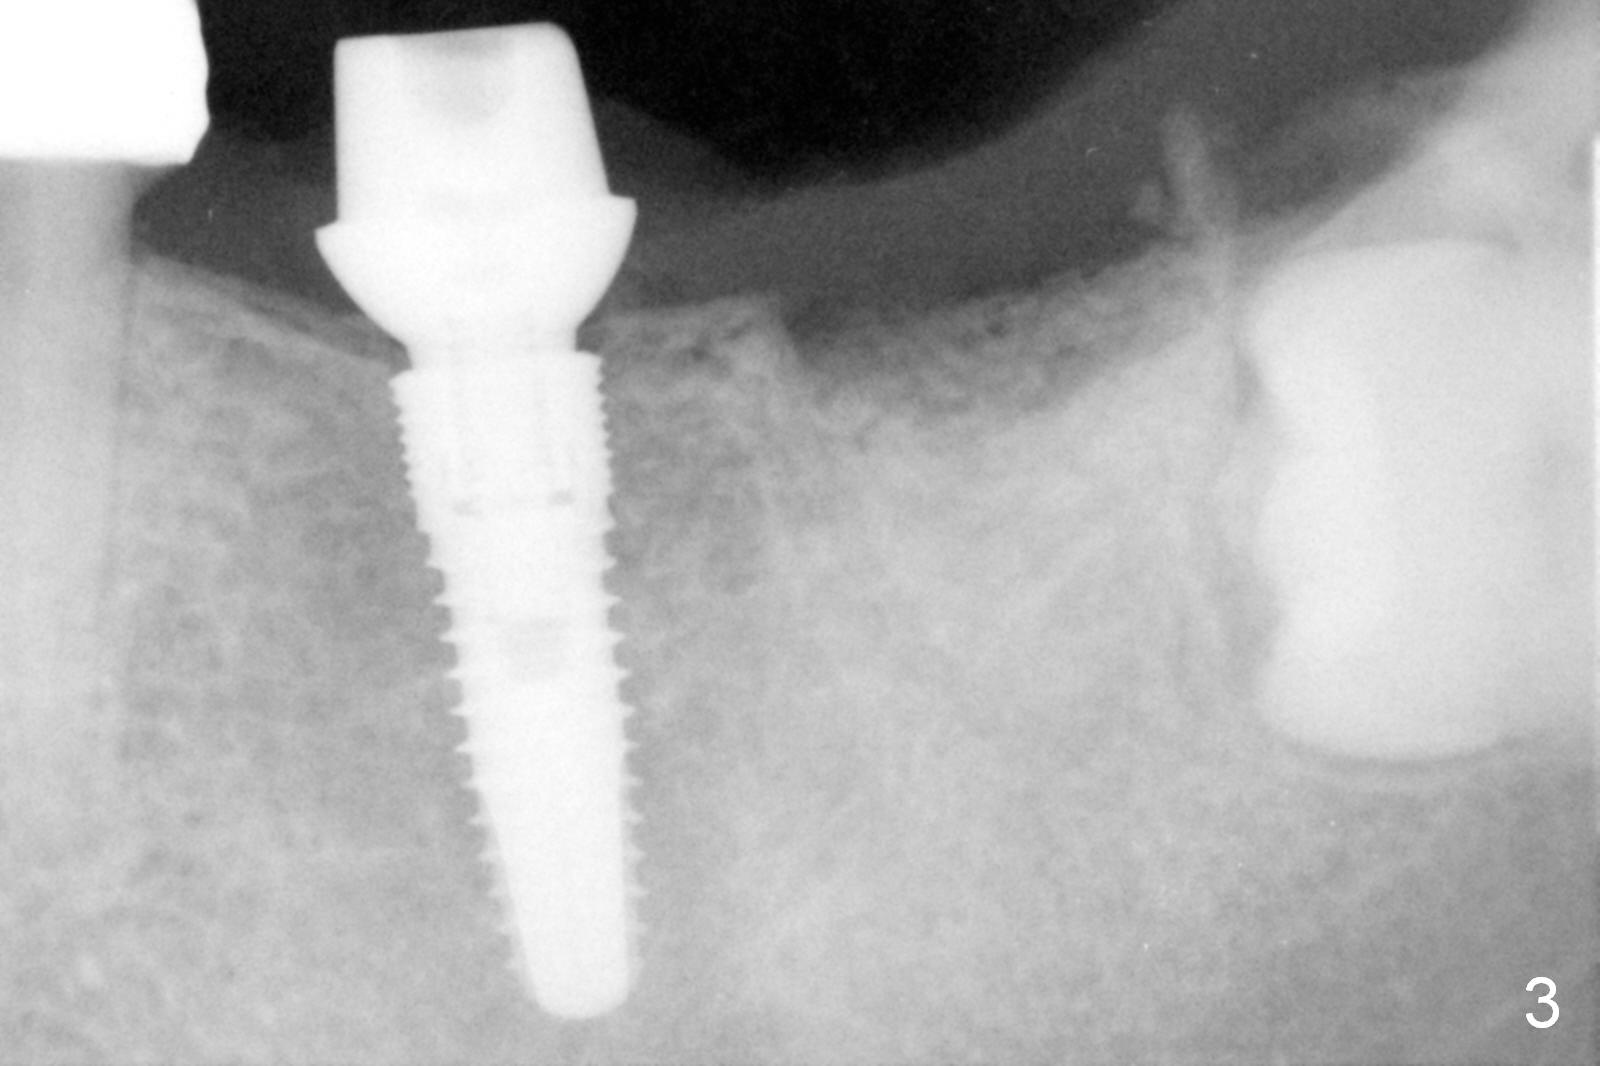

Infiltration anesthesia is enough for initial osteotomy at the site of #19 (Fig.1), but not for sectioning the tooth #18. Block anesthesia has to be administered. Fortunately it is safe to start osteotomy at #18 (~ 3 mm beyond the socket bottom, Fig.1 (red dashed line: the superior border of the Inferior Alveolar Canal (IAC))). A 4.5x14 mm implant is stable at #19, while a 5x12 mm one at #18 is not (Fig.2). Unfortunately bone graft has been placed. When the implant is removed, a 4.5x14 mm drill is used to deepen the osteotomy for 2 mm. The patient reports mild discomfort later on. Hemorrhage occurs, which is stopped when the same implant is re-placed. There is no stability. The implant is removed (Fig.3,4). More bone graft is placed, followed by collagen plug. It appears that bone graft has been pushed into the IAC (Fig.4 arrowheads). Medro dose pak is prescribed. In fact, no paresthesia is reported postop.

When block anesthesia is used, be cautious with implant placement (especially immediate one). Do not deepen osteotomy too readily. Use taps before implant placement. In this case, a larger implant should be inserted.

The patient will return 3.5 months postop. Take PA. Consider using Magic Expanders or Tatum Taper Osteotomes and Tatum or SM taps prior to placing a 5 or 5.3x10 or 12 mm implant. Prepare #15 blade.